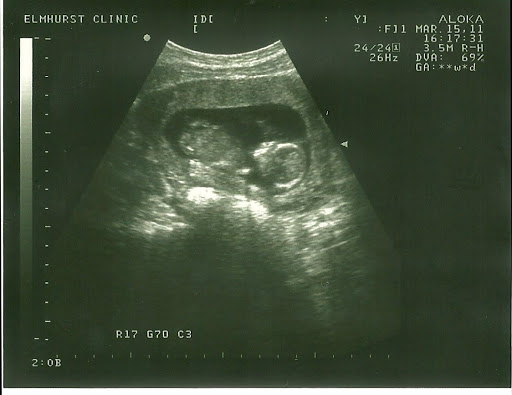

So Jenna and Mark are expecting a baby in September, and when Jenna came and visited me in February, she forgot the ultrasound picture on my fridge. I left it up because I like the idea of having a niece or nephew to spoil rotten and then be able to hand back to Jenna and Mark.